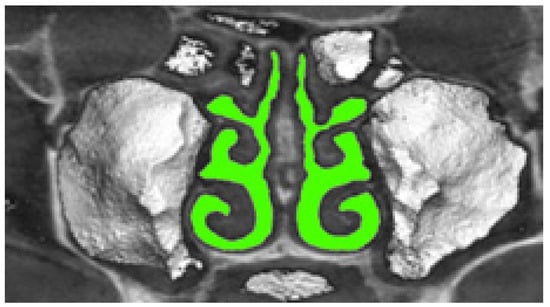

The airway segmentation of the three-dimensional voxel model of the nasal cavity, obtained from tomographic data, is illustrated in Figure 11 and is performed at the intensity T H U A threshold for air density according to the formula (in the soft-tissue window mode we used, the air density threshold was chosen to be less than 0):

c ( x , y , z ) = { 1 ;   i f   b ( x , y , z ) T H U A ; 0 ;   i f   b ( x , y , z ) > T H U A T , ,

where b ( x , y , z ) is the original halftone model of the upper respiratory tract, and c ( x , y , z ) is the binary voxel model of segmented airways of the nasal cavity.

Verification of rhinomanometric data should be performed on the basis of tomographic data of the conditional norm and pathological conditions, which, due to various factors, affect nasal aerodynamics in different ways. Thus, in Figure 12 it is possible to see the characteristic tomographic sections of the nasal cavity at the conditional norm in the axial (Figure 12a) and frontal (Figure 12b) planes.